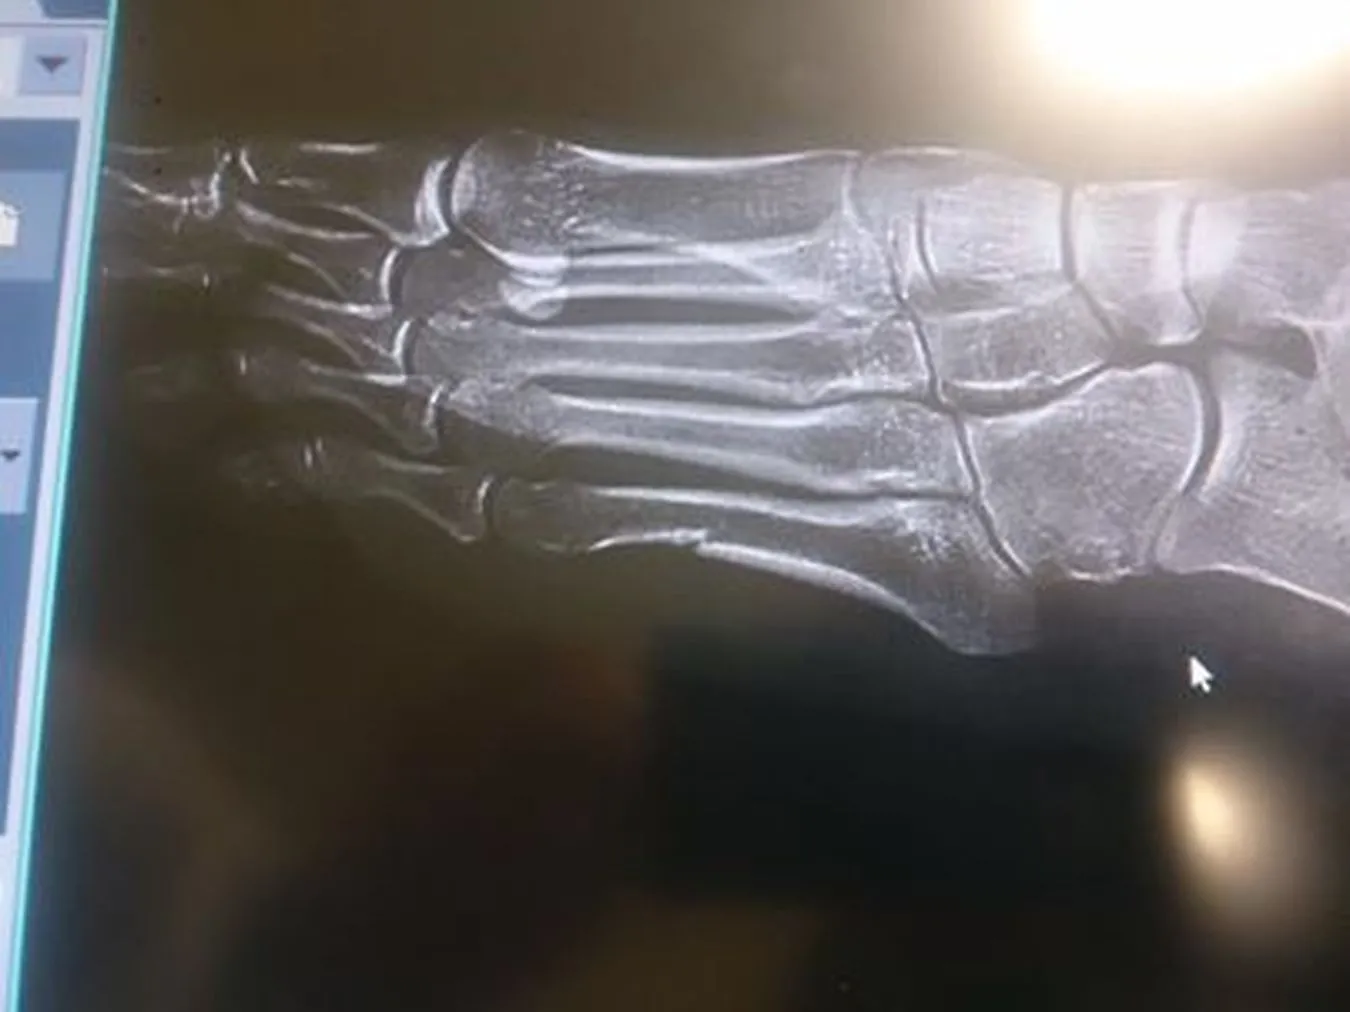

Norwegowie nie wierzą w złamaną stopę Kowalczyk. Podważają autentyczność zdjęcia

14 lutego 2014Norweskie media chyba nie potrafią pogodzić się z porażką. Tamtejsi dziennikarze nie wierzą w złamaną stopę Justyny Kowalczyk i podważają autentyczność zdjęcia rentgenowskiego. Widocznie to, że Polka nawet z kontuzją pokonała ich rodaczki bardzo ich boli.